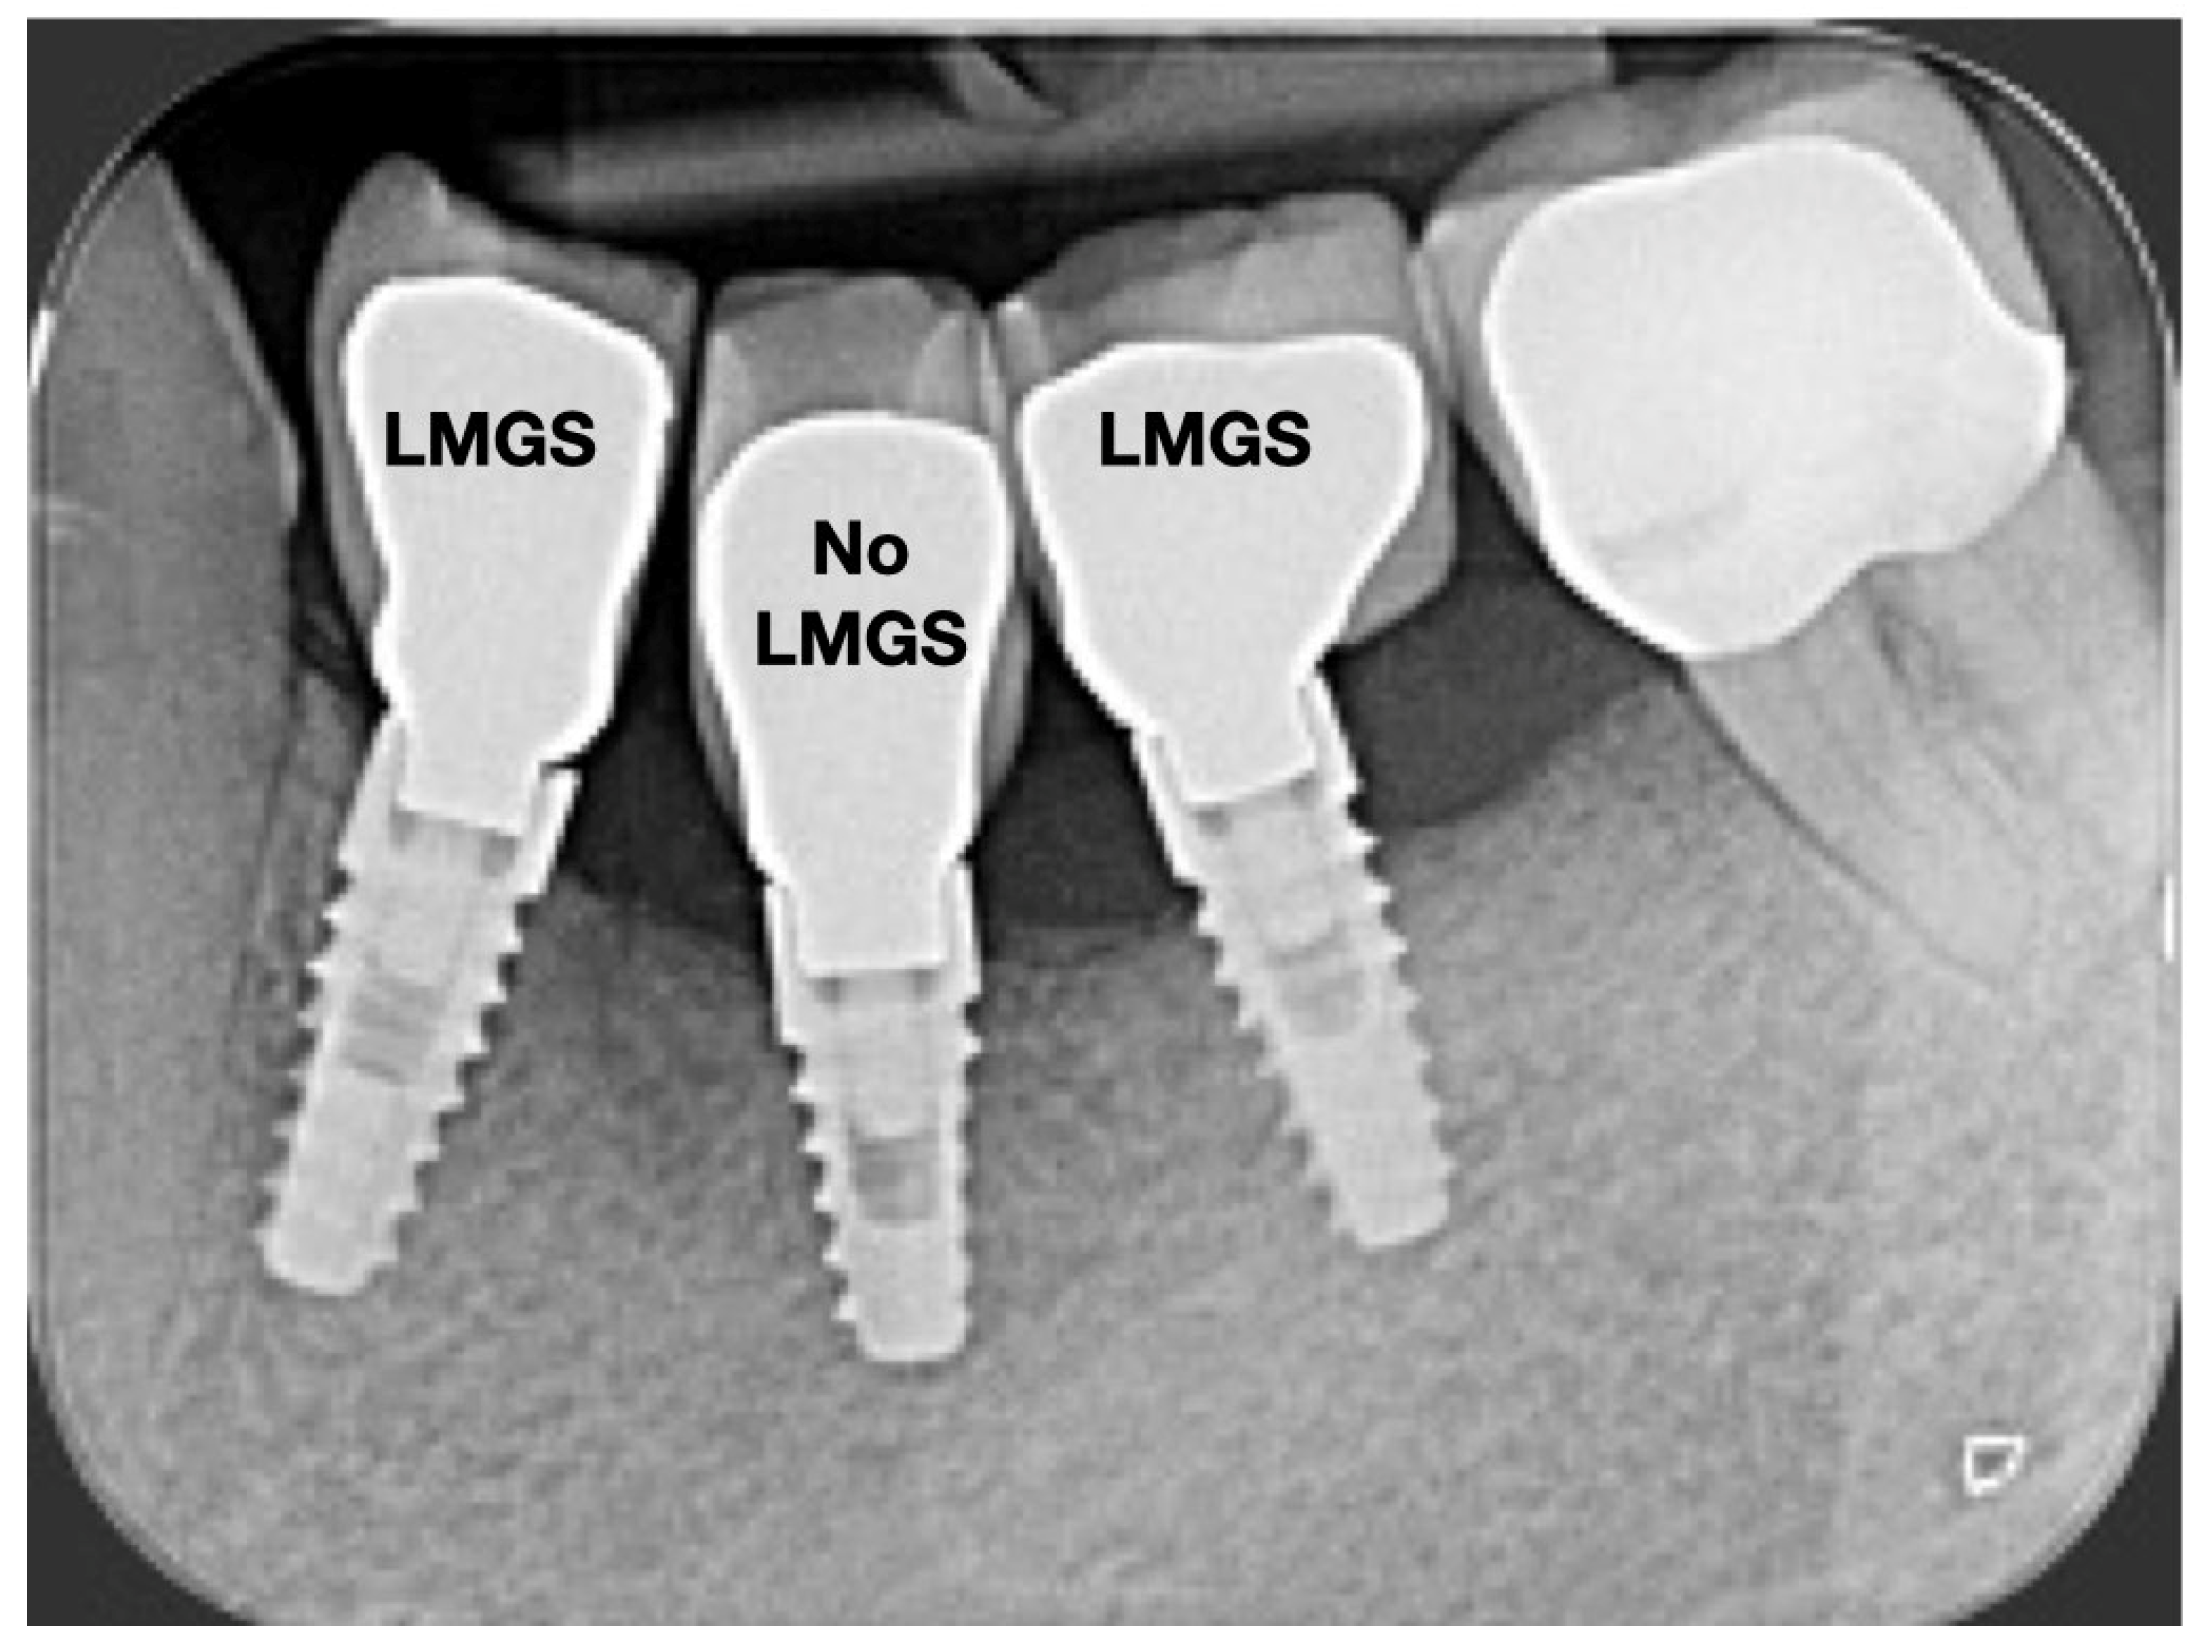

A total of 164 LMGS implants (37.4%) and 195 no-LMGS implants (42.1%) presented PIM. Differences between LMGS implants and no-LMGS implants were not statistically significant (p > 0.05). A total of 28 (6.3%) LMGS implants and 98 (21.1%) no-LMGS implants demonstrated P with a statistically significant difference (p < 0.01). Figure 2, Figure 3, Figure 4 and Figure 5 report examples of radiographs during follow-up.

Figure 3.

Radiograph of the same three (3) implants at 5 years. (LMGS = with a laser-microgrooved collar surface; No-LMGS = without a laser-microgrooved collar surface).